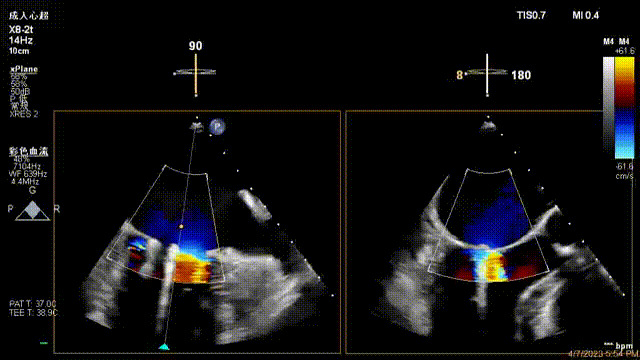

術前超聲提示二尖瓣重度反流

接受治療的是一例器質性重度二尖瓣反流(DMR)患者,主訴“反復活動后胸悶,氣促3年余”。術前超聲顯示,雙房增大,二尖瓣脫垂伴重度反流,輕度三尖瓣反流,輕度肺高壓,升主動脈增寬。手術經股靜脈-房間隔入路,采用全身麻醉插管,在TEE和DSA引導下完成房間隔穿刺。置入JensClip瓣膜夾系統后,在左房調整瓣膜夾的位置和軸向,后進入左室,在TEE引導下捕捉二尖瓣前后瓣葉,并關閉瓣膜夾。經TEE反復確認手術效果后最終鎖定并釋放瓣膜夾。術后即刻超聲顯示瓣膜夾位置穩定,功能良好,術前二尖瓣反流4+,術后0反流,肺靜脈逆流和左房壓都顯著好轉,手術圓滿成功(以上數據都來源于醫院的臨床記錄)。術后患者狀態良好,目前已安排出院。